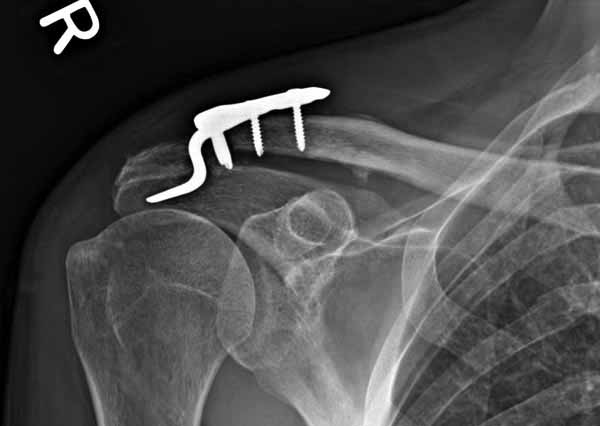

Вложение не в текстовом формате было извлечено…

Имя     : 4 Clavicle AC post op 3.jpg

Тип     : image/jpg

Размер  : 16666 байтов

Описание: отсутствует

Url     : http://weborto.net:8080/pipermail/ortho/attachments/20110623/6adf8600/attachment-0009.jpg